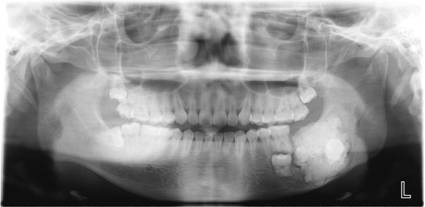

数字化口腔曲面体层片

诊断范围涉及牙体牙髓病、牙周病、阻生牙/多生牙定位、种植牙术前CT评估分析、颞下颌关节CT诊断分析、,颌骨及涎腺疾病、颌面发育畸形、正畸治疗辅助诊断等大部分颌面部疾病,为临床医疗提供强有力的支持。